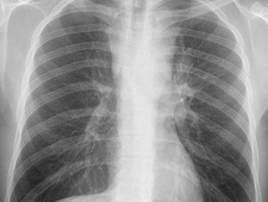

L’examen clinique retrouve une adénopathie sus claviculaire droite.

Biopsie ganglionnaire chirurgicale adénopathie sus-claviculaire: lymphome de Hodgkin classique type cellularité mixte.

VS 96 mm 1ère heure, hémoglobine 10,3 g/dl, globules blancs 16 700, lymphocytes 1200, albumine 34,4 g/l. Biopsie médullaire normale.

Fibroscopie bronchique montre une infiltration tumorale de la lobaire moyenne à son origine et une sténose de la lobaire inférieure droite d’allure extrinsèque. Biopsies de la bronche lobaire moyenne aspect de lymphome de Hodgkin.

Résultat : classement rémission complète conduisant à poursuivre le traitement initialement prévu par BEACOPP renforcé 6 cycles au total, suivis d’une évaluation de fin de traitement pas scanner.